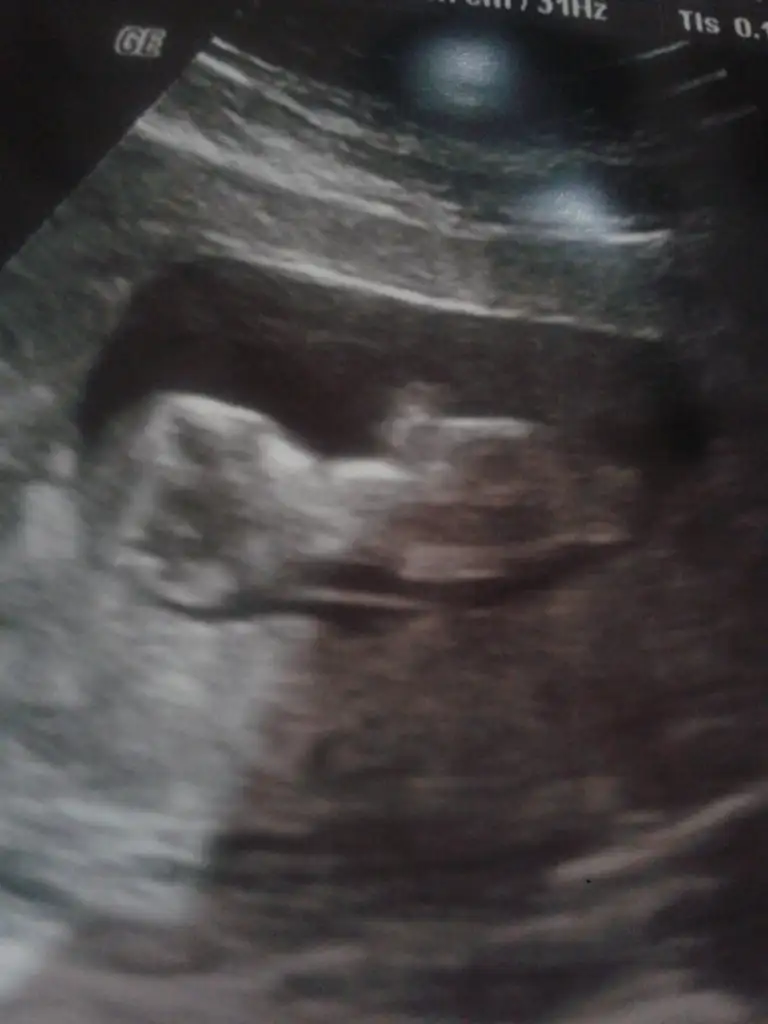

Kızlar bana da yorum yapabilirmisiniz belli oluyor mu bilmiyorum ama açıkçası ben pek anlamıyor bebisim fotoda 12+4 haftalık tüp bebekle oldu sizce cinsiyeti nedir doktor ancak 16. Haftada söyleyebilirim dedi 12 haziranda bir daha ki kontrolüm çok merak ediyorum lütfen yardımcı olun

Kızlar bana da yorum yapabilirmisiniz belli oluyor mu bilmiyorum ama açıkçası ben pek anlamıyor bebisim fotoda 12+4 haftalık tüp bebekle oldu sizce cinsiyeti nedir doktor ancak 16. Haftada söyleyebilirim dedi 12 haziranda bir daha ki kontrolüm çok merak ediyorum lütfen yardımcı olunEki Görüntüle 1528009